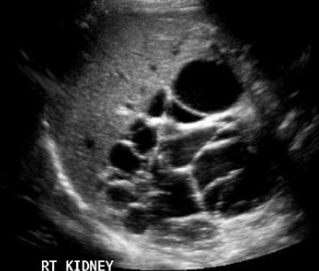

Autosomal Dominant Polycystic Kidney Disease (ADPKD)

More common than ARPKD. Bilateral renal enlargement due to formation of many cysts of various sizes. The cysts gradually enlarge as the patient ages. Over time cysts will compress and destroy normal tissue.

ADPKD indications

Chronic UTI’s, Stone Formation, Back Pain, Headache, Increasing Abdomen Size, High blood pressure, Renal Insufficiency. (50% diagnosed with renal hypertension)(50% will need dialysis or transplant due to renal failure). Increased Bun & Creatinine, Decreased GFR

How is ADPKD usually diagnosed

Typically seen sonographically around 20-30 years of age with sonography, MRI, CT, Xray.

Treatment options for ADPKD

Medications, lifestyle modifications, dialysis, transplant.

Prognosis: Worse as pt gets older due to complications relating to: HTN - Renal Insufficiency and then failure - with a need for dialysis, transplant.

Radiological Images description ADPKD

Cysts may also be present in the liver, pancreas, and/or spleen. Multiple cysts noted.

ADPKD image